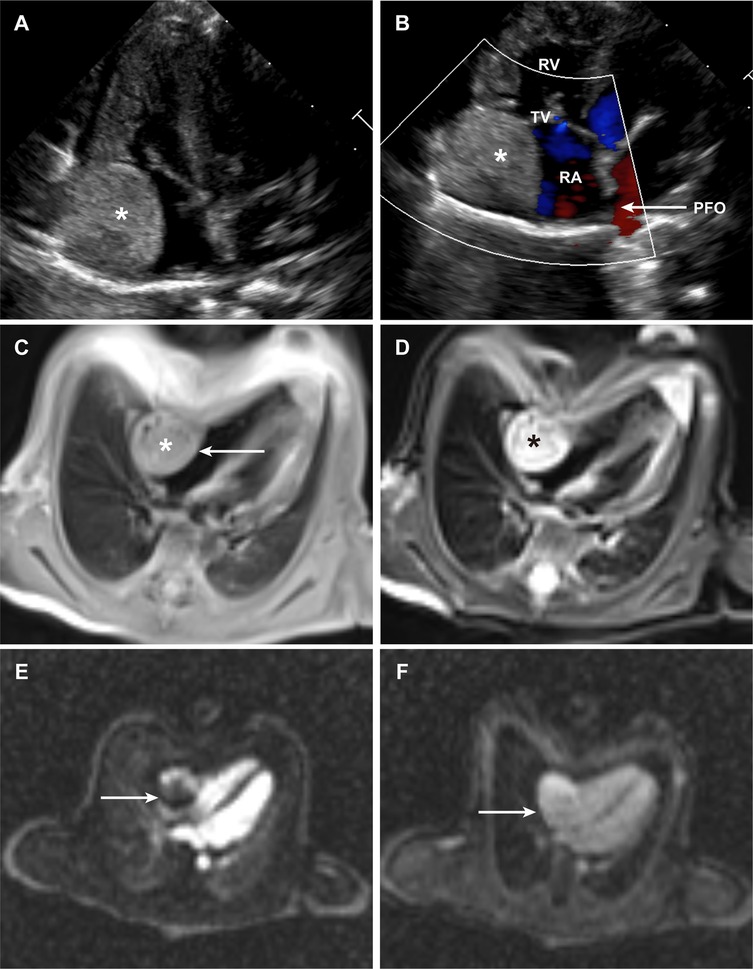

Primary cardiac hemangiomas are extremely rare benign tumors, with limited molecular characterization available. This study investigated a case of mixed-type intracardiac hemangioma in a 17-day-old female neonate, initially detected via prenatal echocardiography and confirmed by postoperative histopathology. The right atrial mass (1.7×2.0×2.1 cm) was surgically resected, and 1-year follow-up, which included transthoracic echocardiography every 3 months and cardiac MRI every 6 months, showed no recurrence and normal cardiac function. Single-cell RNA sequencing was performed on the tumor tissue, yielding 4,888 high-quality cells after quality control. These cells were classified into 9 distinct types, with fibroblasts/myofibroblasts and smooth muscle cells accounting for nearly half the population. Endothelial cells were subdivided into two clusters: Cluster 1, enriched in immune inflammation, cell adhesion, and signal transduction. And Cluster 2, focused on mitochondrial energy metabolism and ribosome biogenesis. InferCNV analysis revealed relative genomic stability, with only minor copy number variations on chromosome 13 in Cluster 1, supporting the tumor's benign nature. Cell communication analysis identified Cluster 1 as the primary effector cell in hemangioma formation, receiving VEGF signals mainly from myeloid-derived suppressor cells and common myeloid progenitors, while also driving collagen synthesis-related pathways. This study provides critical insights into the cellular and molecular mechanisms of cardiac hemangiomas, filling gaps in current understanding of this rare tumor.